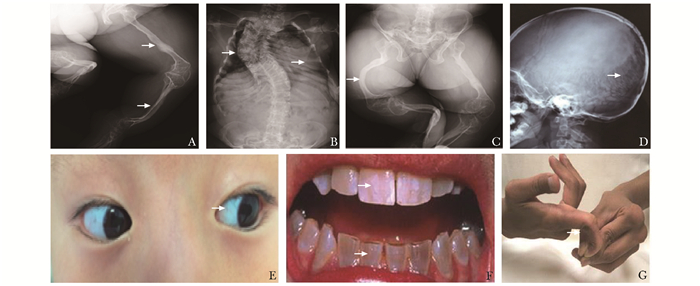

OI的主要临床表现是自幼起病的轻微外力下反复骨折,进行性骨骼畸形,不同程度活动受限。骨骼外表现可以有蓝巩膜、牙本质发育不全、听力下降、韧带松弛、心脏瓣膜病变等(图 2)。骨骼X线影像学特征主要包括:全身多部位骨质稀疏;颅板薄,囟门和颅缝宽,枕骨缝间骨,颅底扁平;椎体变形,多椎体压缩性骨折,脊柱侧凸或后凸畸形;胸廓扭曲、变形,甚至塌陷;四肢长骨纤细、皮质菲薄,骨髓腔相对较大,干骺端增宽,多发长骨骨折,长骨弯曲畸形等(图 2)。

| 图 2 OI患者典型X线表现及常见体征 如箭头所示,A:长骨纤细,皮质菲薄,多发陈旧性骨折;B:脊柱侧凸畸形,胸郭塌陷;C:骨盆畸形,长骨弯曲畸形;D:颅板薄,枕骨缝间骨;E:蓝巩膜;F:牙本质发育不全;G:指间关节韧带松驰;OI:成骨不全症 |